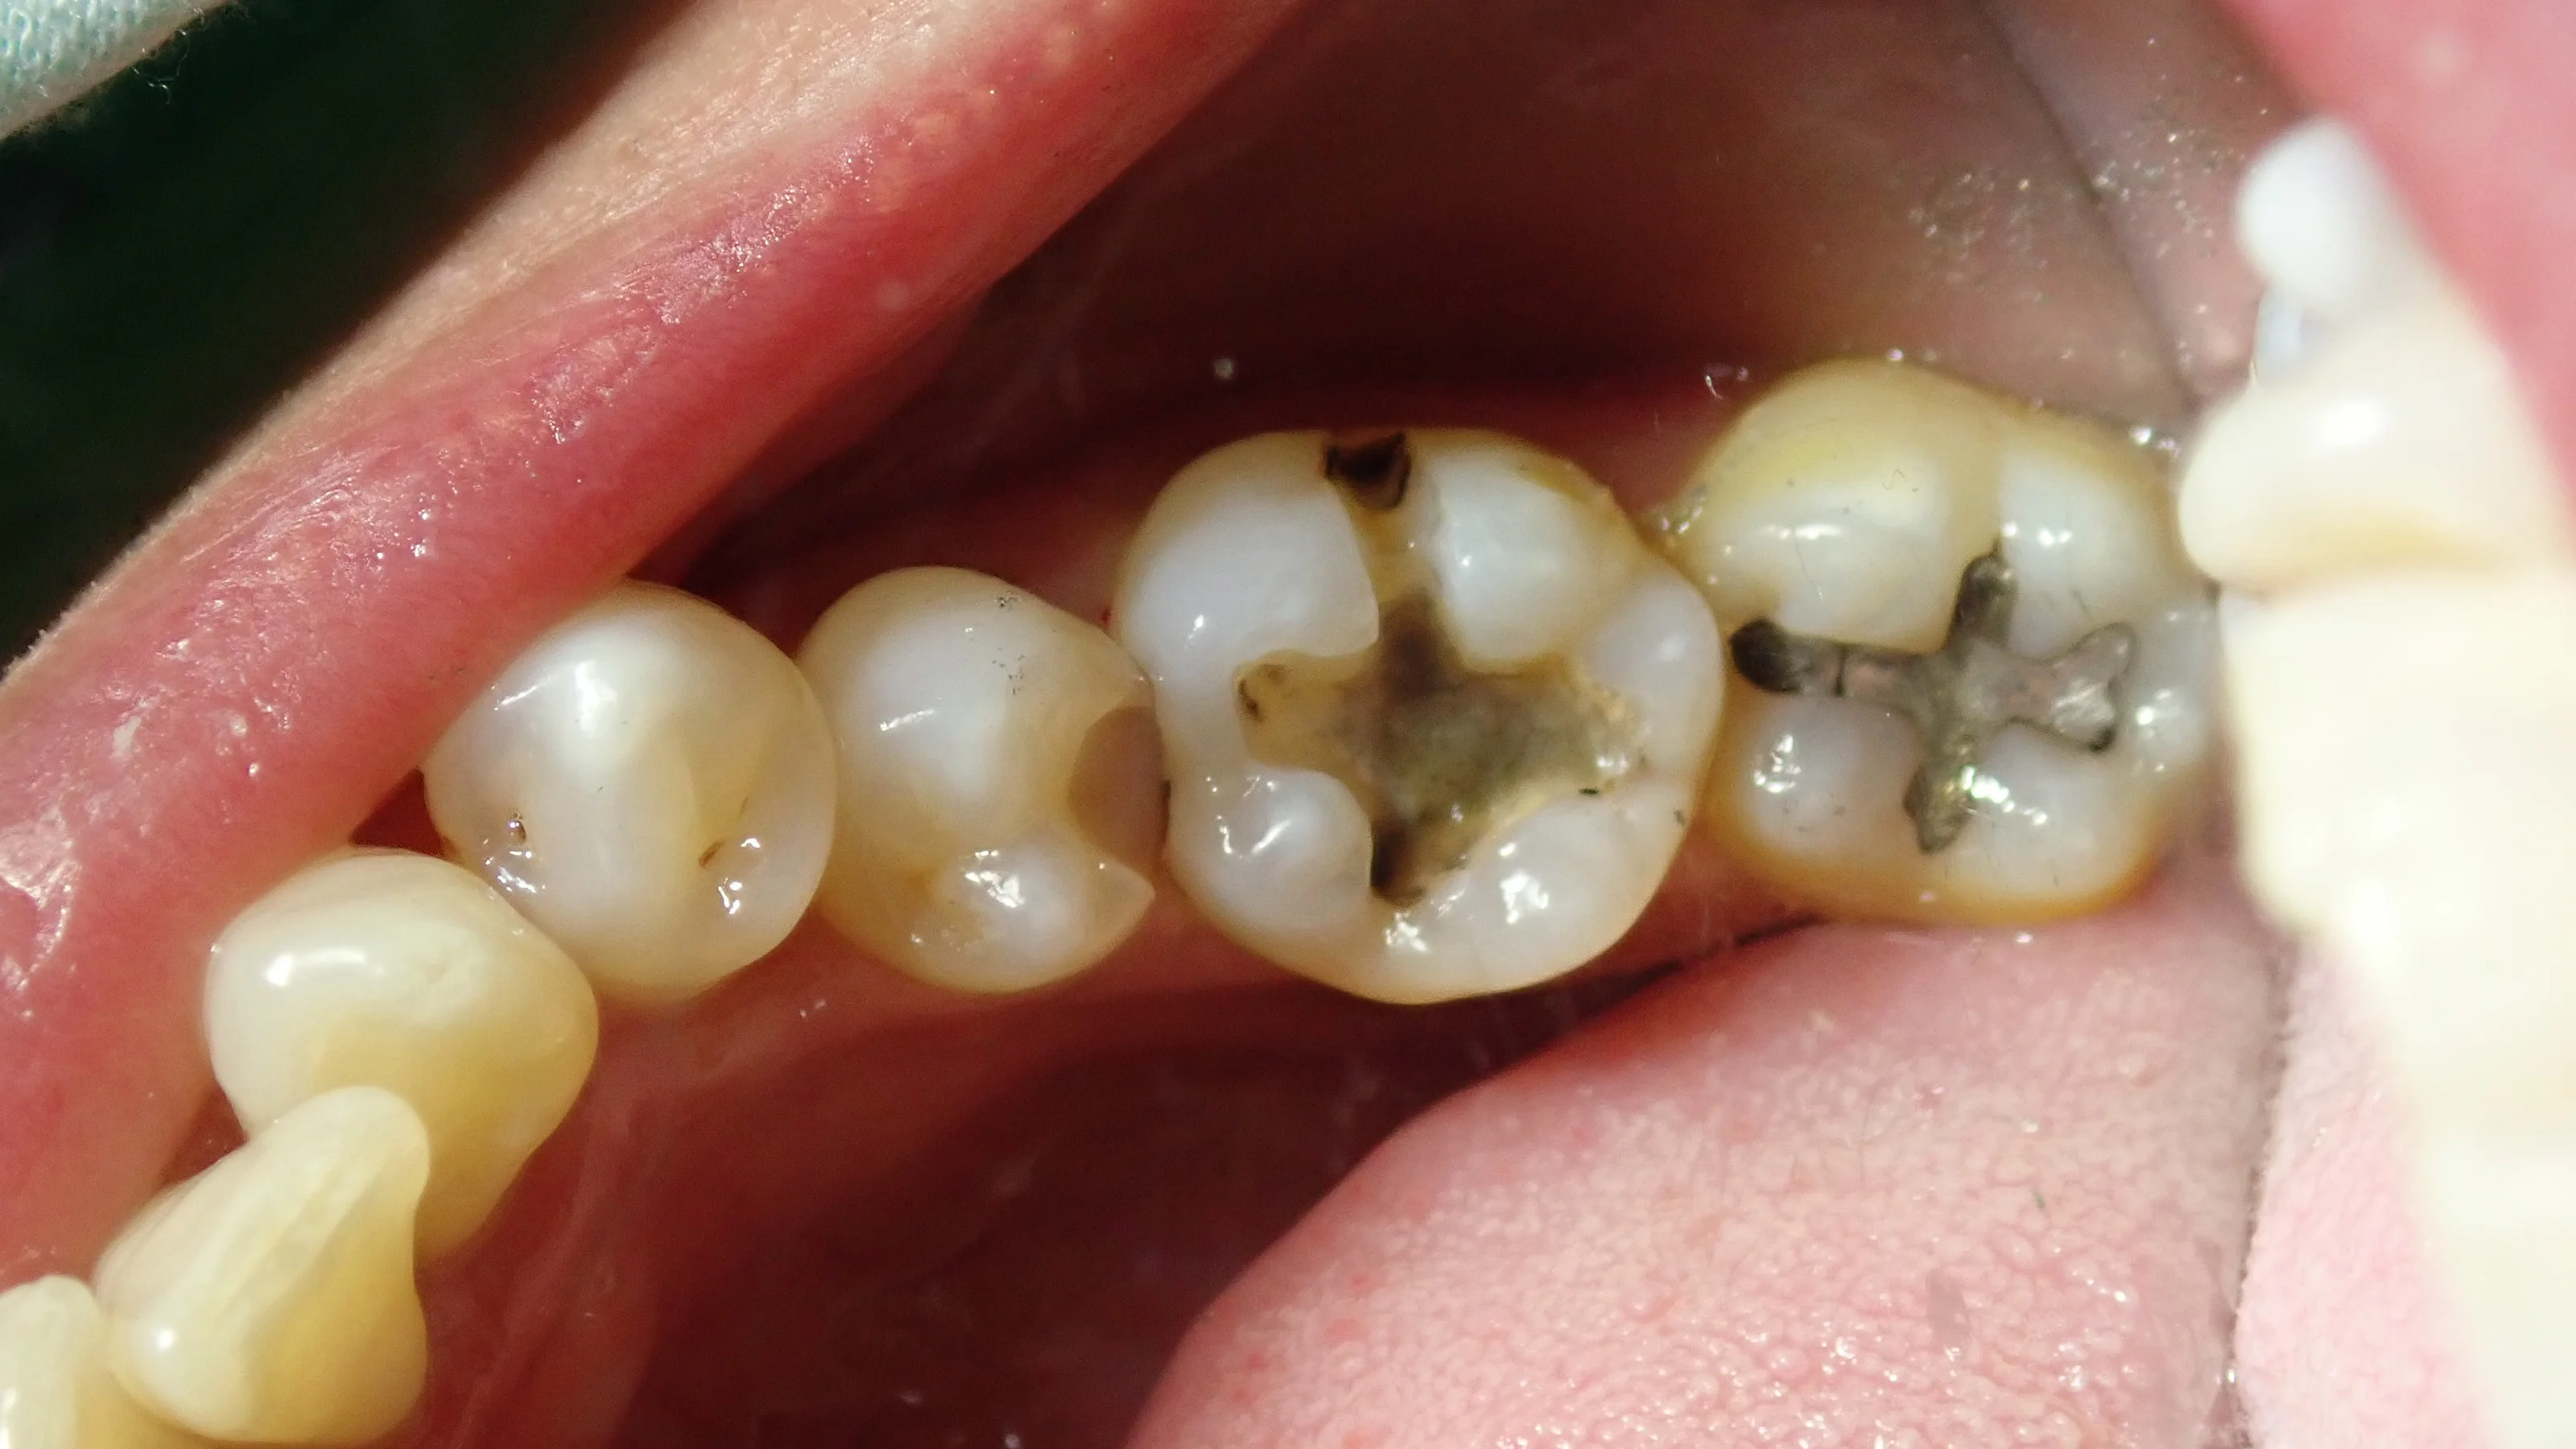

まずは、術前の状態です。

金属の詰め物と、適合のあまり良くない、白い詰め物が入っている場所が今回の治療箇所です。

金属の方は見た目上では虫歯はありませんでしたが、レントゲンにてはっきりと、大きな虫歯になっていたのが確認できました。